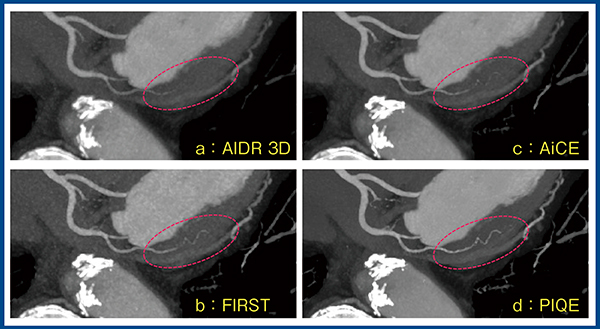

図9はBMI 38.7の高体重症例である。相対的に線量不足となっているが,PIQE(d)では画質が著明に改善し,SDもAIDR 3D(a)の45.0HUに対し,20.8HUまで低下している。冠動脈のcurved MPRにおいても,PIQEでは画質が大きく改善し,読影に耐えうる画像であった。

図9 高体重症例(BMI 38.7)における画質改善